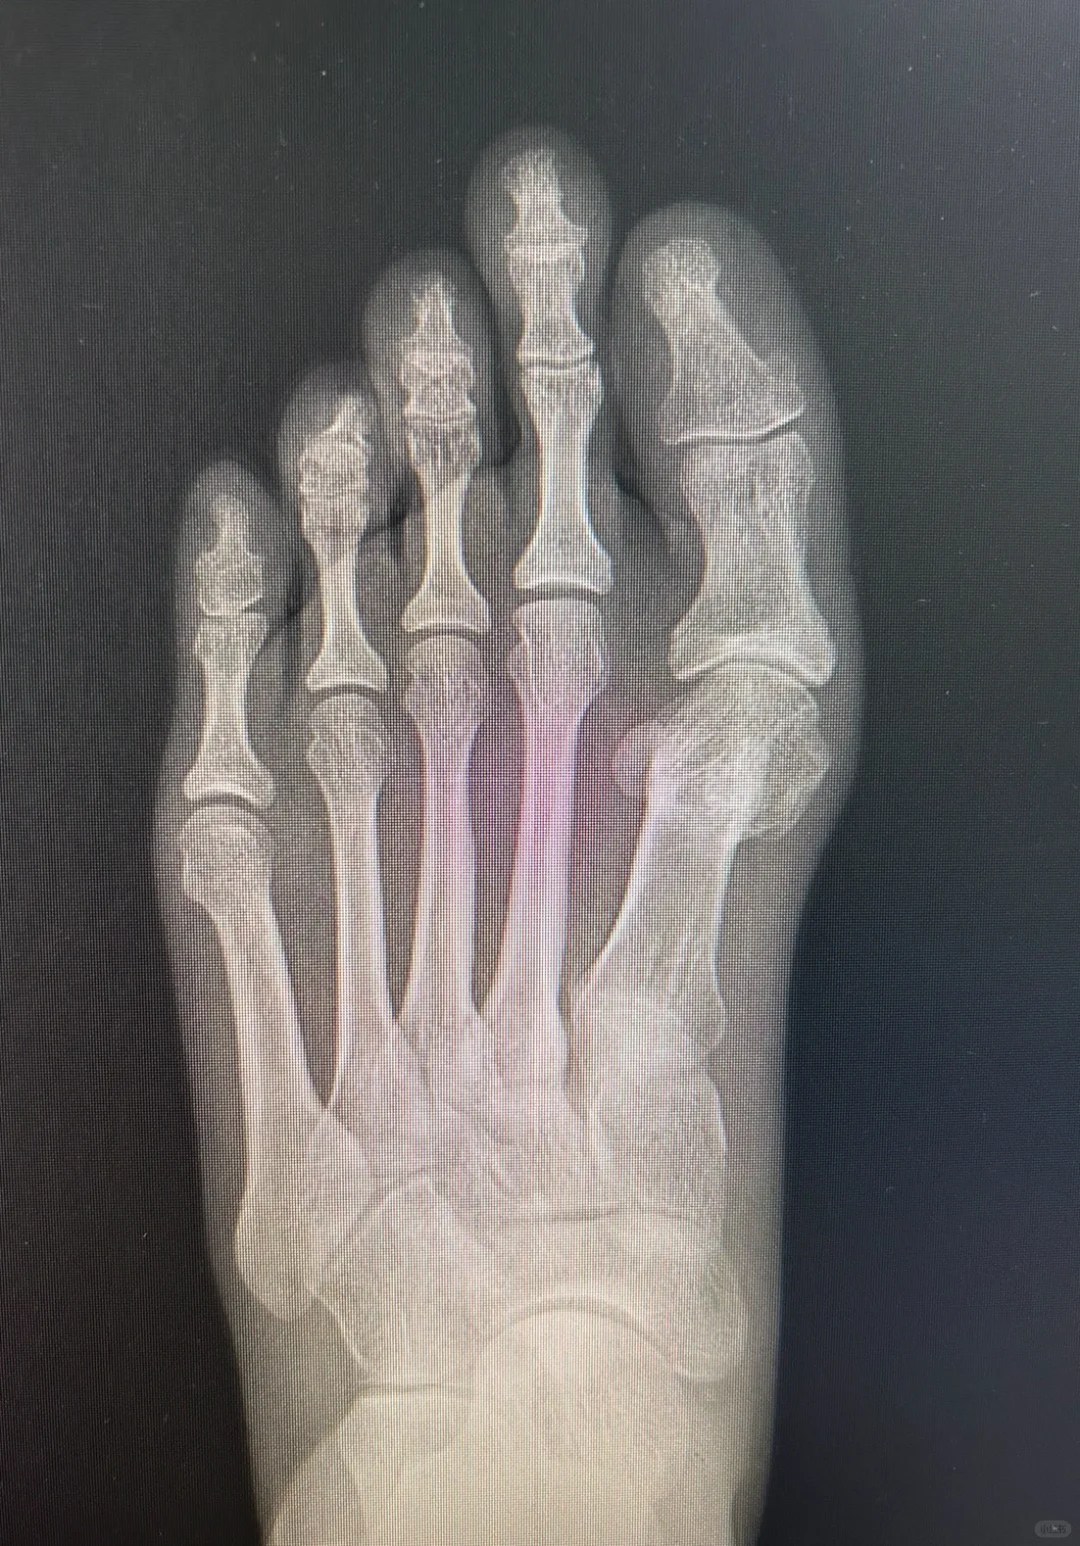

微创术后有一种特殊畸形,就是图中的反旋转畸形。

本来拇外翻畸形就是跖骨向内,也就是向脚心方向出现旋转,我们的手术本来也应该断骨后向二趾方向旋转回来即可。

然而,有的微创医生竟然加大向脚心方向旋转,可以说转错了方向,加大了拇外翻畸形发展。这样有时候可以靠关节周围韧带,让上面的拇趾变直一些,但这种饮鸠止渴的方法会出现很多继发问题。

毕竟不是正常的骨关节结构,而且很容易出现关节炎。